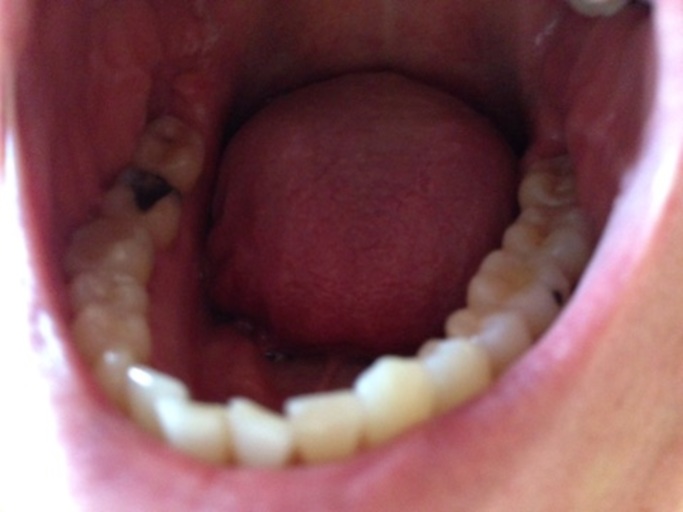

Black spots on teeth

Hi, I haven't been to the dentist in 2 years after a bad experience, stupid I know. I have booked a dentist appointment for Thursday but I am scared. I have recently notices small black spots between some of my teeth and am just scared about what these could be. My teeth used to bleed but I have bought corsodyl toothpaste last week and the bleeding has stopped. Other than that, my teeth do not hurt, and I don't have any receeding gums. And my teeth look healthy other then that. Thanks a lot

Answer: Dark spots on teeth

You took the first step by scheduling an appointment. The dark areas you are seeing could be a number of things. First, since it has been sometime since your last professional dental cleaning, it may be plaque or tartar buildup that is beginning to stain from food and drinks. Second, it could be the start of a carious lesion, or interproximal decay. This is a cavity that forms in between the teeth as a result of not flossing and removing the harmful plaque and bacteria. Third, it can just be stain. At your appointment, they will take dental xrays called bitewings that check for decay in between the teeth. It is best to catch these areas and have them restored if necessary when they are small. Be sure to floss at least once a day to reduce your chances of interproximal caries.